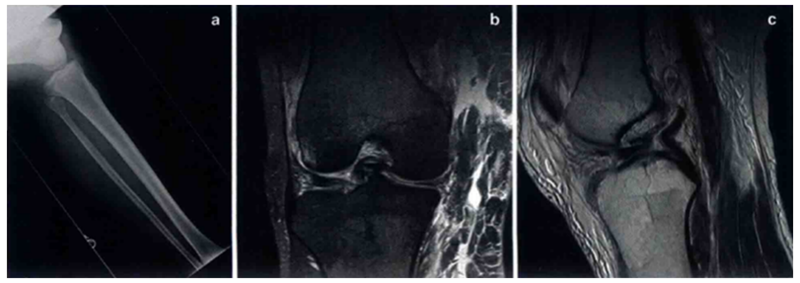

在全面的体格检查后,应当进行正、侧位X线检查,以诊断骨折和评估胫骨股骨移位。术后X线检查可用于评估复位后关节力线是否恢复。MRI在鉴定损伤的结构、程度和部位上十分有用。尽管MRI在协助确定是否手术和手术计划时十分有用,但仍然不能取代全而的体格检查(图2)。

图2 a为同一个患者的膝关节脱位时的X线片。b冠状位和c矢状位MRI显示ACL、PCL和半月板桶柄状撕裂。冠状位还显示MCL损伤